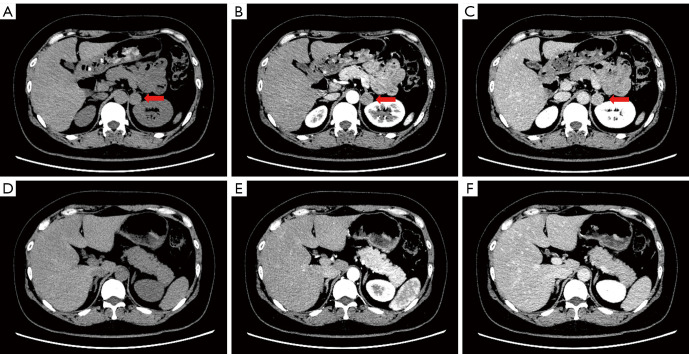

Results: Between September 2023 and September 2024, 73 patients underwent unilateral adrenalectomy guided by AVS at our institution, with CYP11B2 IHC successfully performed in 63 cases. Among these, 21 patients (33.33%) achieved bilateral AVS success, 20 (31.75%) demonstrated unilateral AVS success, and 22 (34.92%) exhibited bilateral AVS failure. Pathological analysis of the bilateral AVS success group revealed aldosterone-producing adenoma (APA) in 12 cases, aldosterone-producing micronodule (APM) in 1, multiple-aldosterone-producing micronodules/nodules (MAPM/MAPN) in 2, aldosterone-producing diffuse hyperplasia (APDH) in 1, APA with MAPM in 3, and APA with APDH in 2. In this group, complete and partial clinical success rates were 47.62% (10/21) and 52.38% (11/21), respectively, while biochemical success rates reached 95.24% (20/21) for complete and 4.76% (1/21) for partial success. The unilateral AVS success cohort included APA (n=8), aldosterone-producing nodule (APN) (n=2), MAPM/MAPN (n=3), APA with MAPM (n=4), APA with APDH (n=2), and 1 CYP11B2 IHC-negative lesion, with clinical success rates of 40.00% (8/20) complete and 60.00% (12/20) partial, alongside 90.00% (18/20) complete and 10.00% (2/20) partial biochemical success. The bilateral AVS failure group comprised APA (n=8), MAPM/MAPN (n=1), APA with MAPM (n=5), APA with APDH (n=2), and 6 CYP11B2 IHC-negative lesions, demonstrating 36.36% (8/22) complete, 50.00% (11/22) partial, and 13.64% (3/22) no clinical success, with biochemical outcomes of 72.73% (16/22) complete, 18.18% (4/22) partial, and 9.09% (2/22) no success. Notably, bilateral AVS success correlated with significantly superior biochemical outcomes compared to bilateral failure (P=0.045).

Conclusions: Adrenalectomy guided by AVS yields better outcomes in patients with PA when AVS is successful on both sides compared to those with bilateral AVS failure. The source of excess aldosterone secretion on the dominant side identified by AVS is not necessarily an APA/APN. It may also include MAPM/MAPN, diffuse adrenal cortical hyperplasia, and various complex combined conditions. In patients with bilateral AVS failure, adrenal specimens more frequently exhibit negative immunohistochemical staining for CYP11B2.